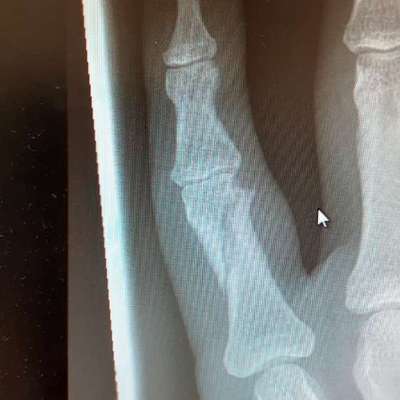

Ich biete Kleinfinger gebrochen, da hatten wir zelda noch keine 8 Wochen und sie gat nen Satz zur Seite gemacht und die Leine ist zwischen Ring und kleinfinger geraten. Aktuell einen Muskelfaserriss beim Agility in ein Loch getreten und es hat geknallt im Oberschenkel 🫣